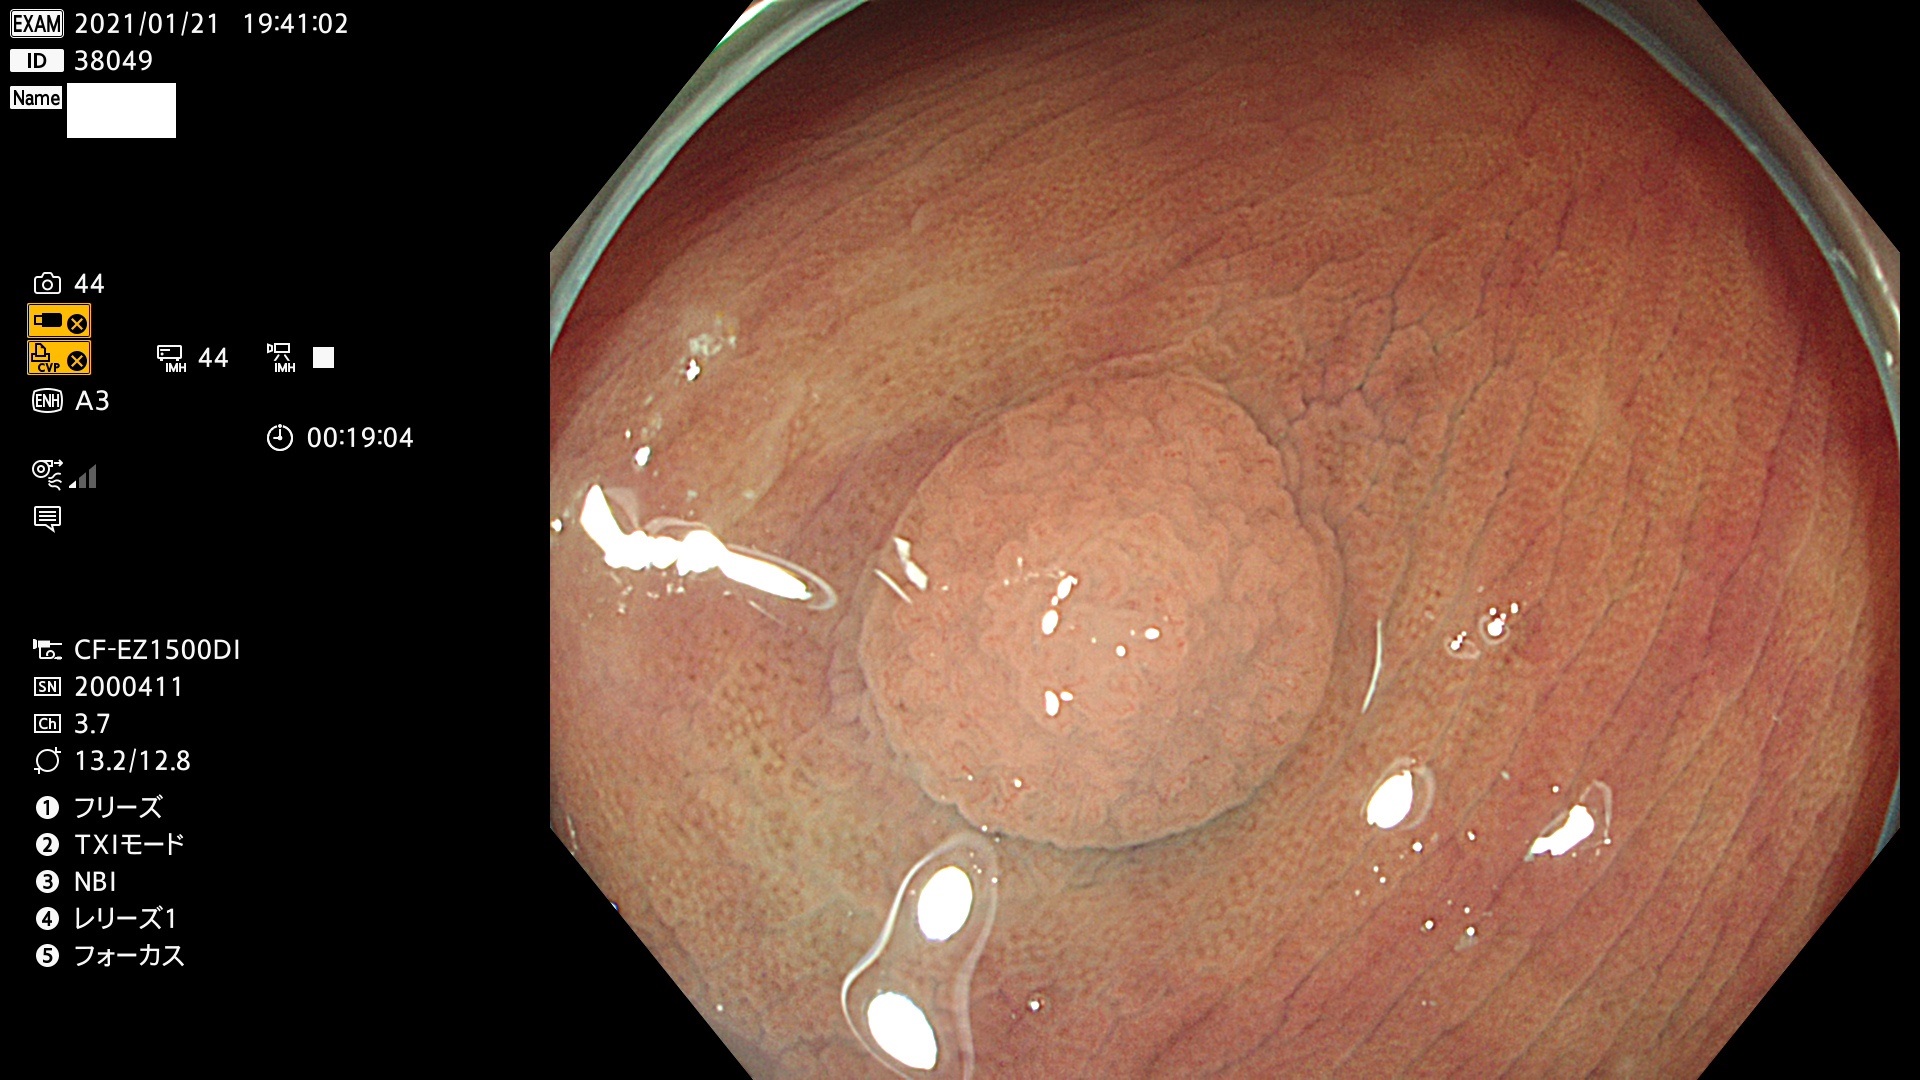

38001 38002 38003 38004 38006(SSAPのみ) 38007 38008 38009 38010 38012 38013 38014 38016 38018 38020 38021 38025 38026 38029 38032 38033 38034 38035 38036 38037(SSAPのみ) 38039 38043 38044 38048 38049 38050 38052 38055 38056 38057 38058 38059 38064(SSAPのみ) 38065 38068 38069 38070 38071 38072 38074 38075 38076 38078 38079 38080 38082 38083 38084 38085(SSAPのみ) 38086 38087 38088 38089 38090 38091 38092 38093 38094 38097 38098 38099

発見困難で危険性の高い平坦型病変(上記100名より抽出)